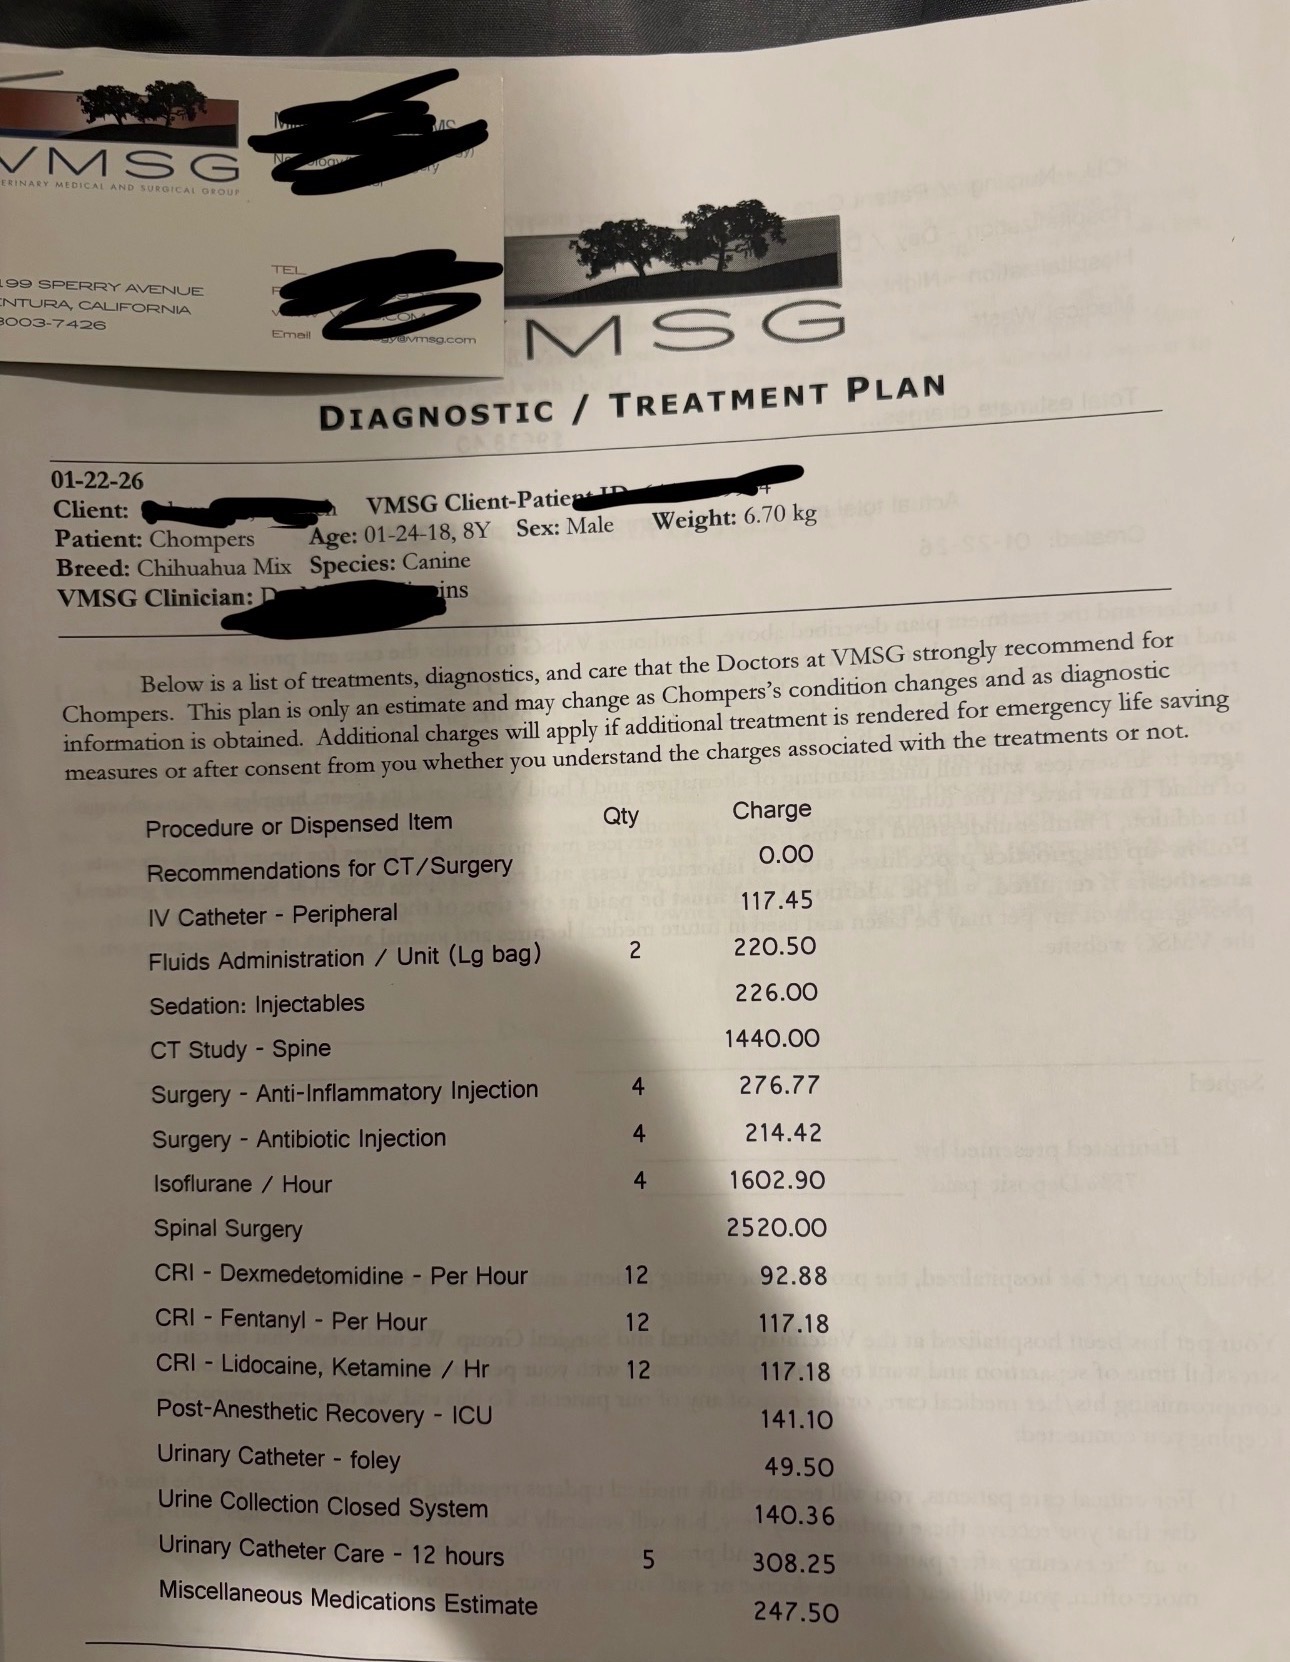

After multiple emergency veterinary visits, lab work, radiographs, CT imaging, and a neurology consultation at Veterinary Medical & Surgical Group (VMSG), Chompers was diagnosed with severe intervertebral disc disease (IVDD) with a confirmed herniated disc compressing his spinal cord.

The total estimated cost for Chompers’ emergency care and spinal surgery is $10,161.91, based on official hospital estimates and invoices. This includes emergency care, advanced imaging, neurology consultation, surgery, anesthesia, ICU recovery, medications, and post-operative care. I am attaching all medical records and invoices for full transparency.